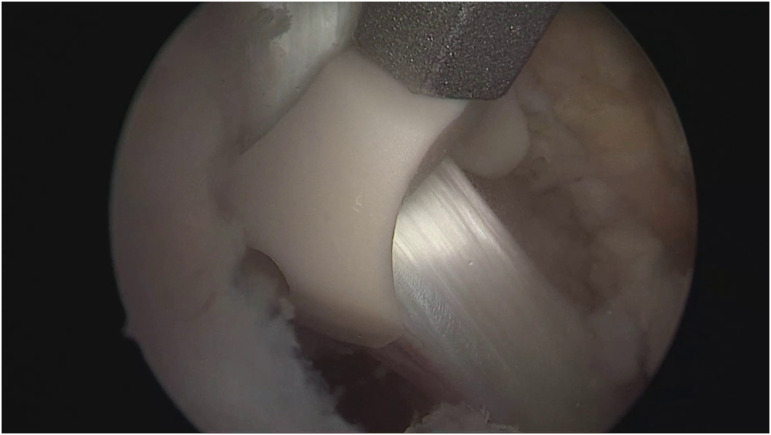

Objective: While many biomechanical studies have compared various biotenodesis materials for biceps tenodesis, there is a lack of research comparing different types of interference screws. This study aimed to compare the impact of a polyether ether ketone (PEEK) forked eyelet tenodesis screw with the traditional PEEK closed eyelet whipstitching technique. The focus was on evaluating the occurrence of Popeye deformity, which is an objective predictor of a successful arthroscopic suprapectoral long head of biceps tenodesis. Methods: A retrospective analysis was conducted on patients who underwent arthroscopic rotator cuff repair and biceps tenodesis performed by a single surgeon between January 2010 and 2020 at a single center. The follow-up period was at least 1 year. Exclusion criteria included previous shoulder surgery and osteoarthritis. Patients were divided into 2 groups based on the type of tenodesis anchor used: forked eyelet tenodesis screw versus closed eyelet tenodesis screw. The occurrence of Popeye deformity was compared between the 2 groups. Results: A total of 82 patients who underwent arthroscopic rotator cuff repair and biceps tenodesis were evaluated, with a mean follow-up of 24.5 ± 4 months. The patients operated on using forked eyelet tenodesis screw were labeled as Group I (n=72) and those with traditional PEEK closed eyelet screw as Group II (n=10). There were no significant differences between the groups in terms of age (Group I: 59.4 ± 5, Group II: 58.4 ± 4, P=.896), gender (both groups predominantly male, P=.886), and body mass index (Group I: 26.7 ± 2, Group II: 27 ± 3; P=.896). The overall rate of popeye deformity in all patients was 8% (n=7). No significant difference in popeye deformity occurrence was observed between the 2 groups (Group I: 6/72 (8.3%), Group II: 1/10 (10%); P=.998). Conclusion: The incidence of Popeye deformity after arthroscopic biceps tenodesis in patients undergoing concomitant rotator cuff repair is low. The choice of fixation anchor, whether a forked eyelet or closed eyelet PEEK anchor, does not significantly influence the occurrence of Popeye deformity. Level of Evidence: Level III, Therapeutic study.